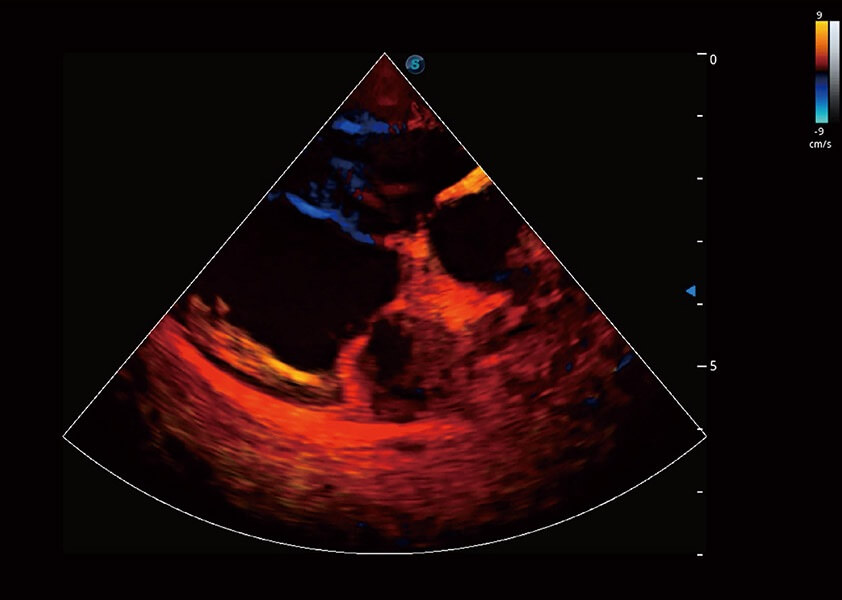

优异的基础图像

(犬)四腔心血流

4T血流成像 微察秋毫

融合不同血流成像技术的优势,即可以提升血流成束性,同时可提高血流的视觉敏感性。

Bright Flow 立体血流成像

在传统二维血流成像的基础上,呈现血流的立体感,具有动感的生命力之美。精确区分不同血管的空间关系,提高了血流的视觉敏感性。